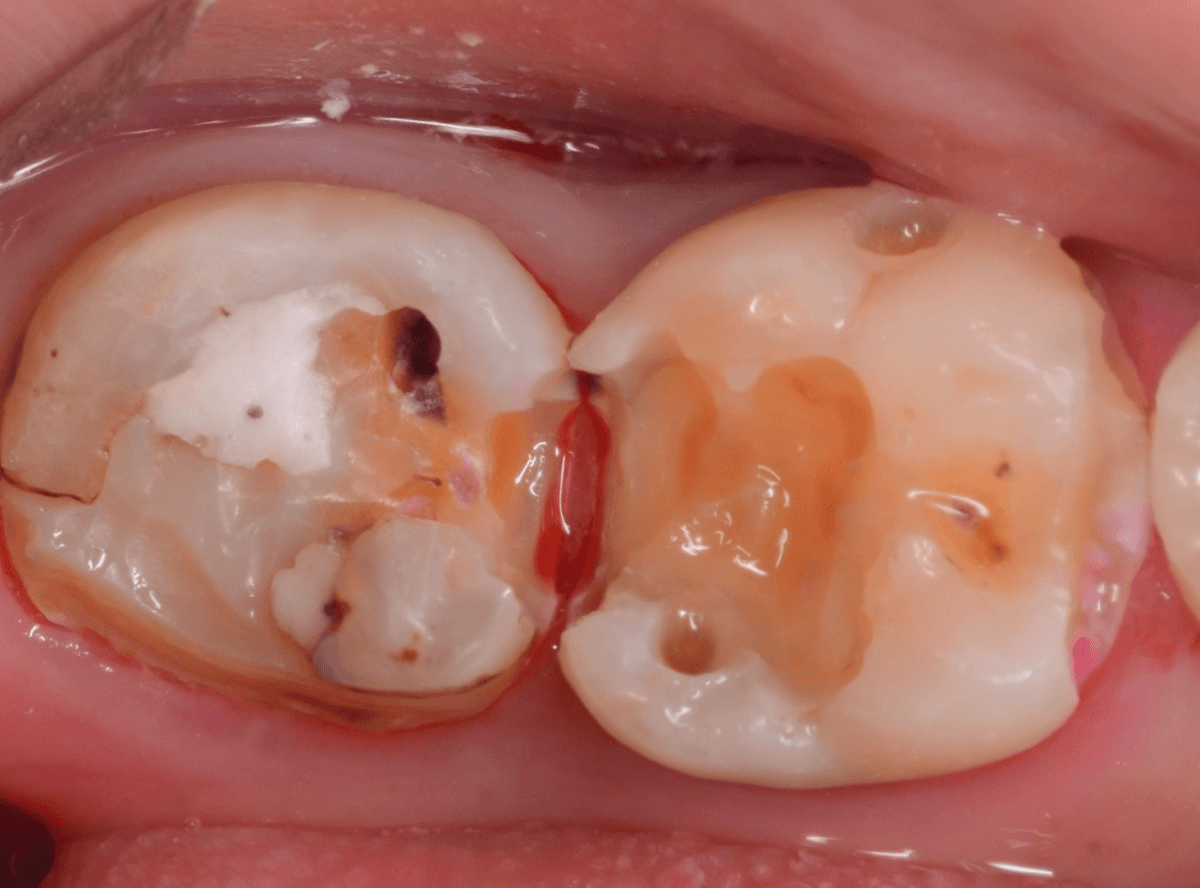

麻酔をして、治療を開始します。

レジンを外すと、中から出血してきました。

これは、歯のスキマに歯肉が入り込んでしまったために起こってしまったものです。

おそらく、随分前から虫歯が進行していたと思われます。

止血しながら、電気メスで歯の中に入り込んだ歯肉を除去します。

虫歯と入り込んだ歯肉でぐちゃぐちゃになっている状態でした。

これでは、痛みが出てもおかしくありません。

慎重に全ての虫歯を除去したところです。

〇部が神経の入り口が見えているところです。

神経を保護する処置をして、しばらく経過観察しますが、痛みが出て神経を除去する必要が出る可能性も高いです。